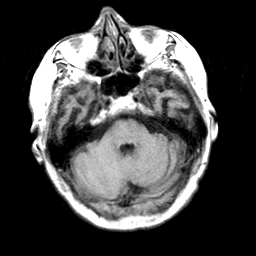

Pick's Disease, MR Study mr-t1 -- Slice #5

[Home][Help][Clinical] Slice 5